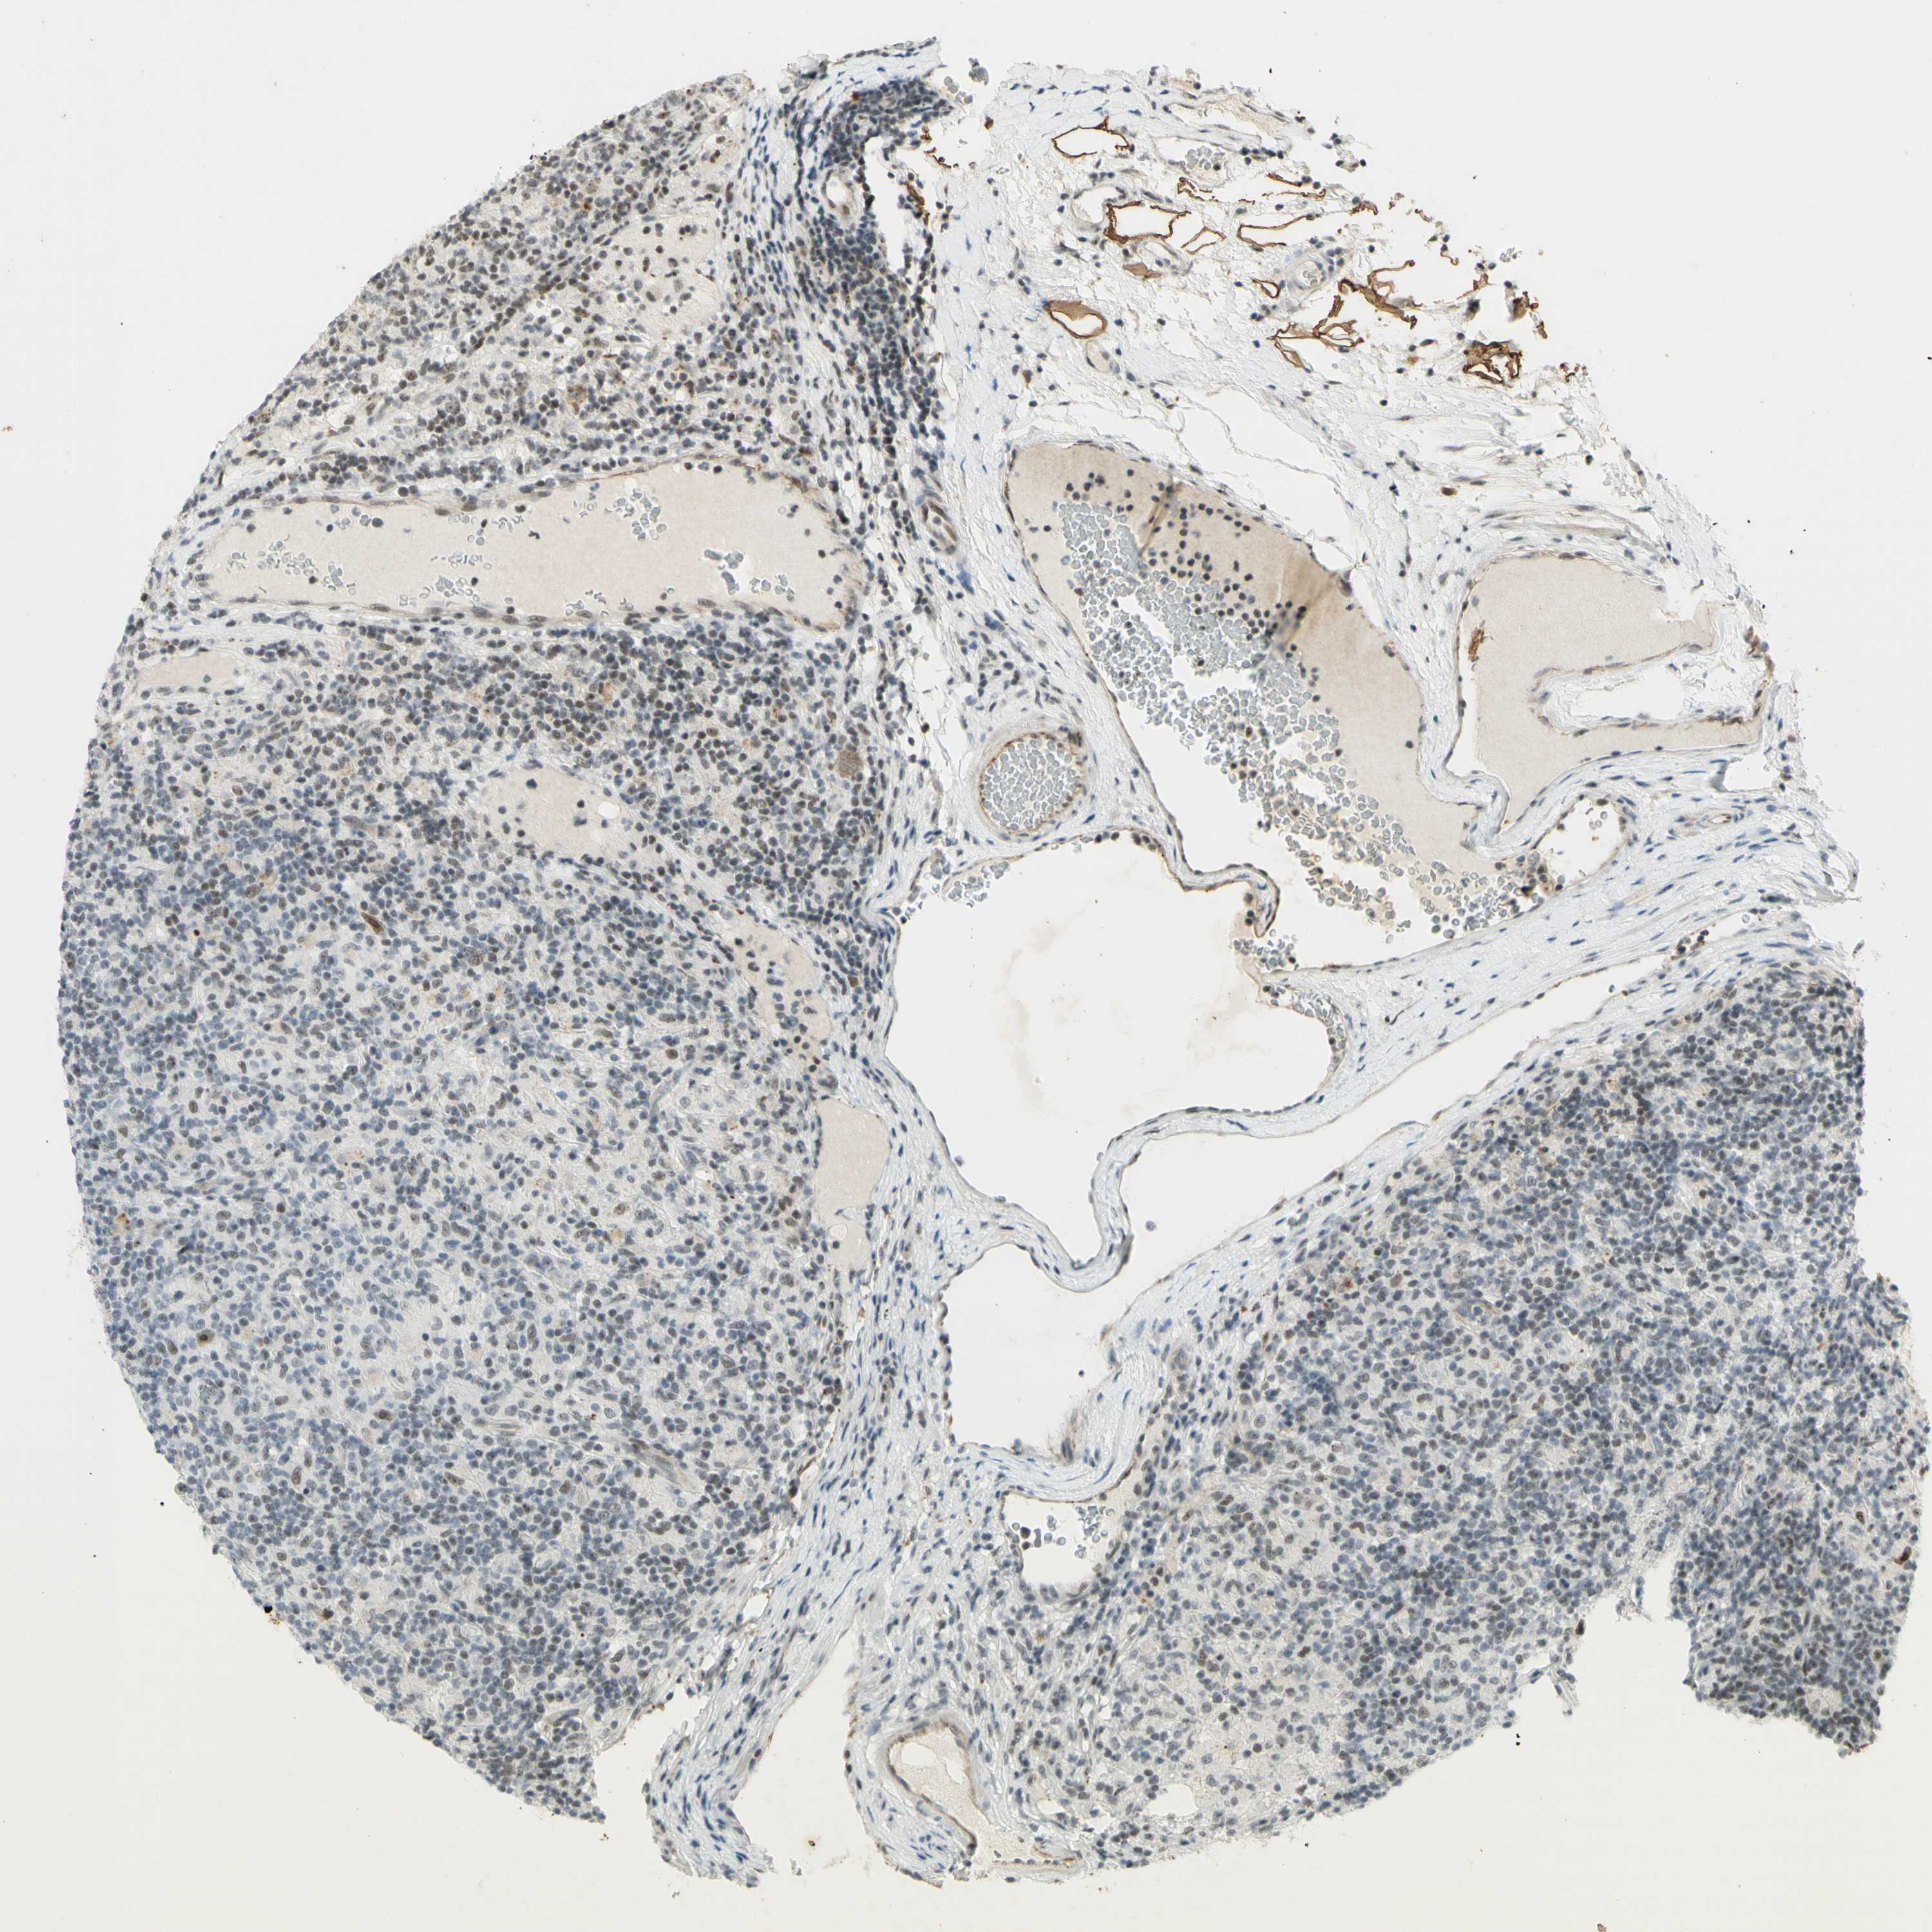

LYMPHOMA - Protein expressioni

A mouse-over function shows sample information and annotation data. Click on an image to view it in a full screen mode. Samples can be filtered based on level of antibody staining by selecting one or several of the following categories: high, medium, low and not detected. The assay and annotation is described here.

Antibody staining in the annotated cell types in the current human tissue is reported as not detected, low, medium, or high, based on conventional immunohistochemistry profiling in selected tissues. This score is based on the combination of the staining intensity and fraction of stained cells.

Each image is clickable and will lead to virtual microscopy that enables deeper exploration of all samples and also displays staining intensity scores, fraction scores and subcellular localization as well as patient and tissue information for each sample.

Antibody HPA063131

Antibody CAB011662

Malignant lymphoma, non-Hodgkin's type, Low grade

Malignant lymphoma, non-Hodgkin's type, High grade

Hodgkin's disease, NOS

Hodgkin's lymphoma, nodular sclerosis